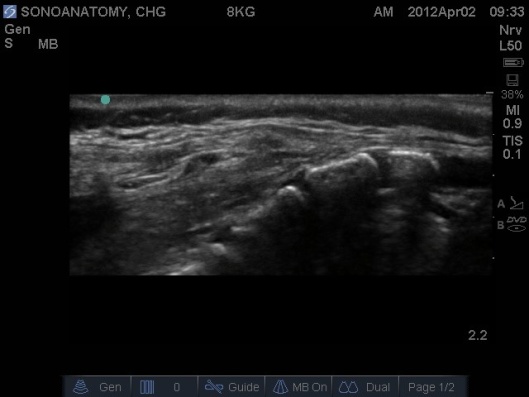

Fig 4. Ultrasound Probe in Midline Longitudinal position over sacrum.

- Prior to performing the caudal a ‘Mapping’ or ‘Scout’ scan is performed to assess the position of the dural sac in relation to the sacrococcygeal membrane. The angle of needle/cannula insertion can be observed. See Figs 1-7.